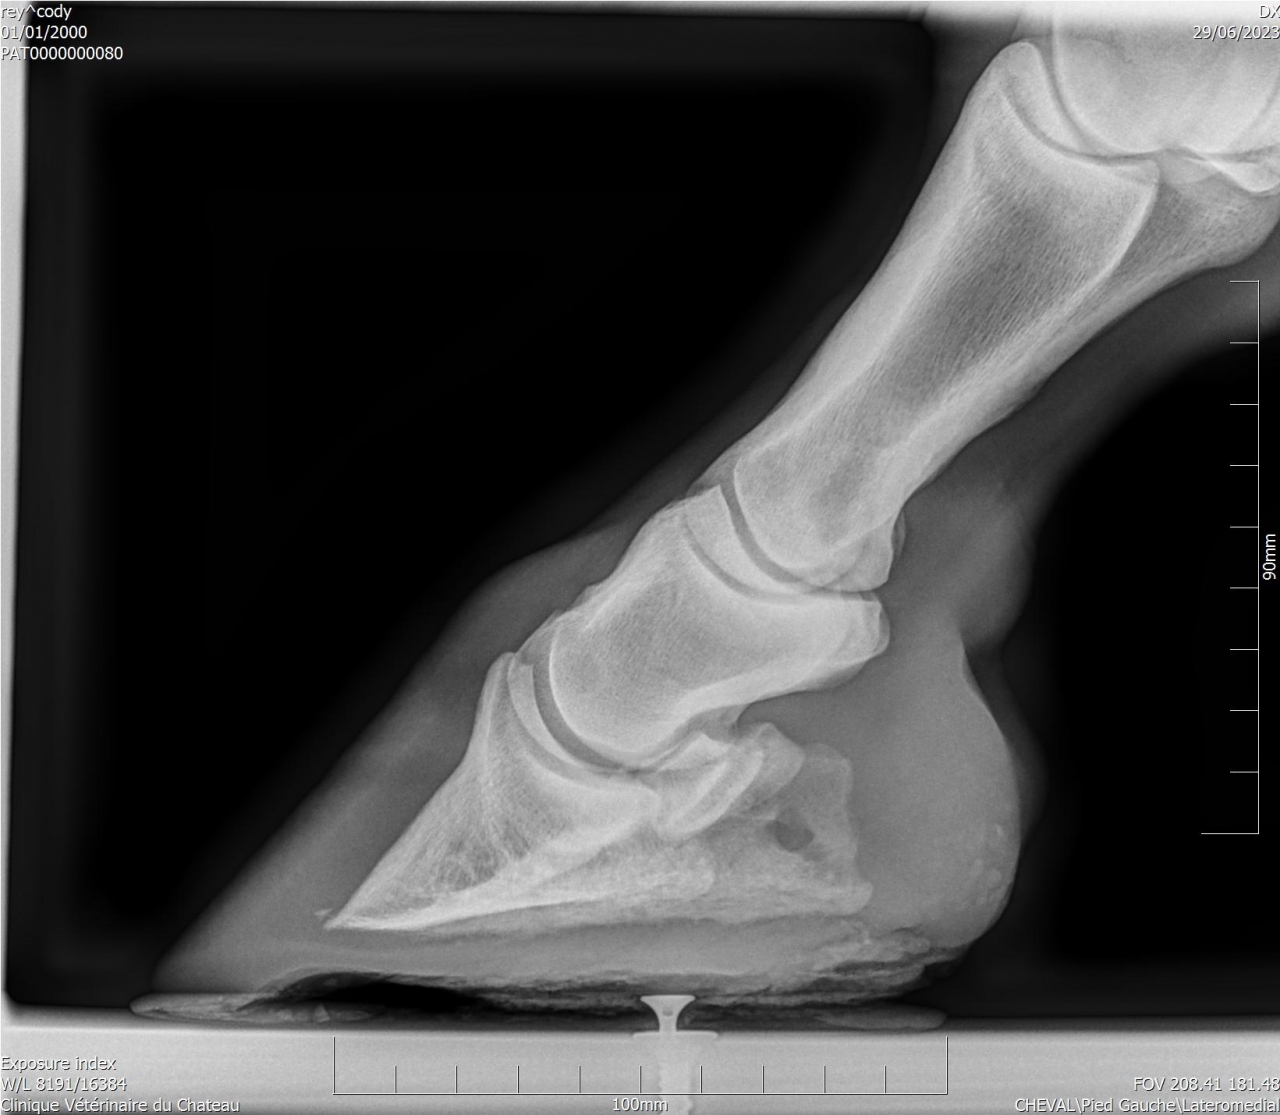

| Dire merci | Je suppose très fortement que les vibrations sont douloureuses. J’ai même dû le faire tranquiliser lors de l'avant dernier ferrage. La dernière fois avec les anti inflammatoires (inflacam) ça s’était bien passé. Mardi j’ai donné du rheumoxidil mais je ne l’ai donné qu’une heure avant au lieu de 2 ... Cody a une ossification des processus palmaires aux 2 antérieurs. Il est trop sensible pieds nus sur sol dur (même au pré) que j’ai dû me résoudre à le ferrer. J’ai testé les hipposandales et ça n’a rien changé. Il est beaucoup mieux avec ce "nouveau" maréchal ferrant qui met des fers en aluminium avec plaques en cuir. Le précédent faisait une ferrure oignon et aucune différence flagrante avec pieds nus. |

Par goss_de_panloup : le 02/11/24 à 20:39:15

| Dire merci | Aucun des vétos consultés n’a été capable de donner une explication à la boiterie et à la douleur au ferrage ... Voici des radios de l’année dernière : ![]() ![]() Si quelqu'un a une bonne adresse de spécialiste en Isère je prends. |

| Dire merci | Tu as une radio LM par hasard ? |

| Dire merci | Un cheval qui bosse pas, qui a juste 10 ans et qui a une locomotion dégradée selon les jours, ça pue l arthrose précoce, le naviculaire ou chais pas quoi. Il te faut un vrai bilan ds une clinique qui sait faire les radios et échos et qui sait les lire |